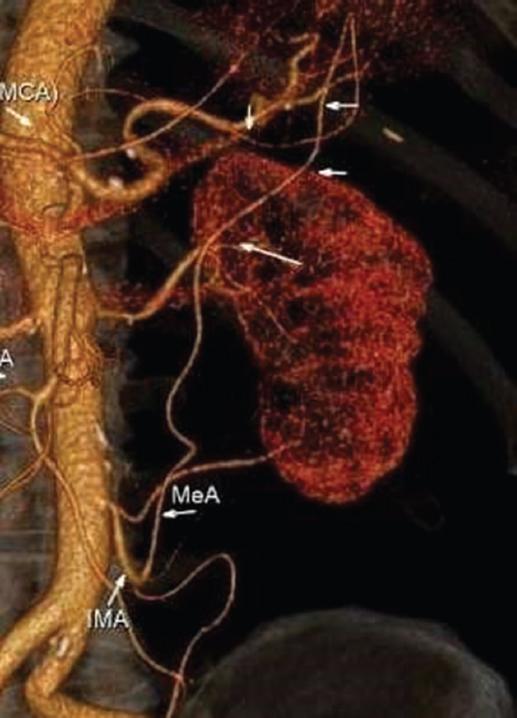

Figure 2 Three-dimensional-computed tomography angiography: Moskovich’s artery marked by arrows (MeA). IMA: inferior mesenteric artery; MCA: middle colic artery.

The Moshkovich’s artery, also known as the tortuous mesenteric artery, is a lesser-known collateral route and is another link between the SMA and IMA. The Moshkovich’s artery runs along the base of the mesentery of the colon and is the connecting link between the proximal segment of the MCA and the ascending branch of the LCA2,6. In our study, we found the presence of this artery in only 1 (1%) patient (Fig. 2 and 3).